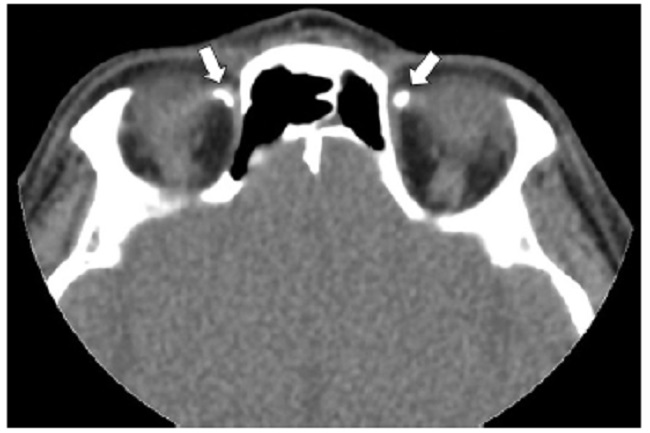

Los cambios postratamiento y los dispositivos orbitarios también pueden malinterpretarse como patologías traumáticas. Dentro de estos cambios se incluyen la faquectomía con reemplazo del cristalino, las hebillas esclerales (Figs. 19 y 20), las inyecciones intraoculares de aceite de silicona, la retinopexia neumática y las prótesis de globo ocular1,6,11. Para diferenciar la silicona intraocular de hemorragia se ha propuesto la medición de las UH, siendo la atenuación > 100 UH sugerente de silicona y < 90 UH de sangre11 (Fig. 20).